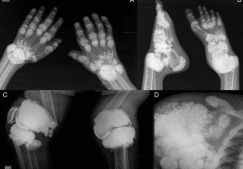

Ревматоидный артрит – хроническое генерализованное аутоиммунное поражение соединительной ткани, поражающее суставы скелета, чаще всего мелкие суставы на руках. Лечение ревматоидного артрита длительное и комплексное, включающее курсы приема нестероидных противовоспалительных средств, гормональных препаратов, цитостатиков. Лечит эту патологию врач-ревматолог. Большое значение имеет также правильный рацион. Диета при ревматоидном артрите не заменяет лечение, но дополняет его и улучшает состояние пациента, увеличивает срок ремиссии и сокращает риск возникновения осложнений.

Для этого заболевания характерно симметричное поражение суставов, как крупных – коленных, локтевых, так и мелких суставов кистей. Суставы кисти поражены в 90% случаев. По мере развития патологии возникает деформация суставов. Кроме сочленений, серопозитивный ревматоидный артрит поражает также соединительную ткань других органов и систем, что вызывает тяжелые нарушения их работы.